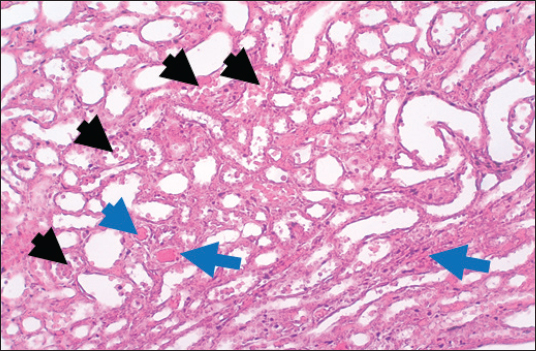

In the control group, histological analysis of kidney sections revealed intact glomeruli and renal tubules (Fig. 1). Conversely, Figure 2 presents a kidney section from the green tea group, which exhibited normal renal tubular epithelial cells, a well-preserved tubular lumen, and an overall normal tubular texture, although some glomeruli showed mild atrophy. The renal section of gentamicin showed atrophy of the glomerular tuft, expansion of the globular space, and significant hyperemia lesions in some glomeruli associated with substantial damage to the superficial cell layer (epithelial cells) in the proximal renal tubules, resulting in a reduction of the tubular lumen space (Fig. 3). In contrast, kidney sections from the gentamicin group that received green tea treatment revealed a marked reveal of both glomeruli and renal tubular epithelium, which appeared normal (Fig. 4 and Fig. 5).

Fig. 4. Kidney of treatment group. The section shows severe hemorrhage (RBCS accumulation in the proximal renal tubules, Black arrows) with ahyperemic lesion in the section of renal tubules (Blue arrows).H and E (10X).